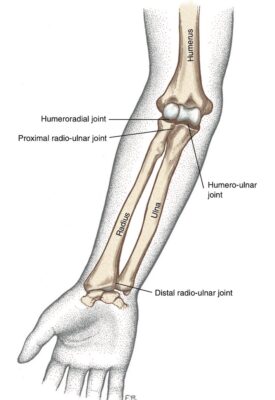

CÁC KHỚP VÙNG KHUỶU- CẲNG TAY

- Hầu hết các vận động chi trên liên quan đến khớp khuỷu và các khớp quay-trụ

- Thường được nhóm với nhau vì có quan hệ giải phẫu gần gũi

2 khớp liên hệ nhau: Khớp cánh tay –trụ: chính, Khớp cánh tay-quay(phụ)

Khớp cẳng tay: quay -trụ (gần –xa)

Là khớp xoay (pivot)

- Đầu gần xương quay xoay quanh đầu gần xương trụ

- Đầu xa xương quay xoay quanh đầu xa xương trụ